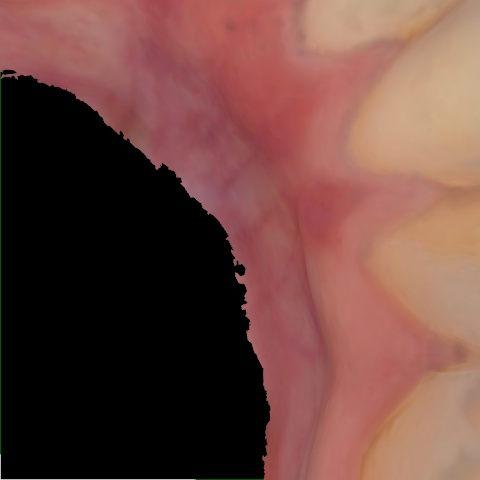

NHD20738

Annotated as "Bad"